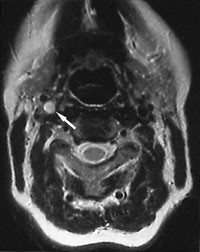

Pasient 3. Kvinne, 50 år. Hun var tidligere frisk. Broren hadde hatt dyp venetrombose i beina, og moren hadde hatt dyp venetrombose i beina og samtidig lungeemboli. Hun hadde båret byggematerialer på høyre skulder, og merket etter dette smerter på høyre side av halsen med utstråling til høyre tinning, og noe sårhet ved svelging. Etter 11 dager fikk hun akutt svakhet og styringsproblemer i venstre arm, og etter hvert ustøhet og kraftsvekkelse i venstre bein, og ble innlagt som øyeblikkelig hjelp. I løpet av tre timer fikk hun også hengende venstre munnvik og talevansker. Ved innleggelse hadde hun dysartri, venstresidig sentral facialisparese og venstresidig hemiparese med paralyse i armen, invertert venstre plantarrefleks og noe nedsatt oppmerksomhet for venstre side. CT av hjernen viste infarkt i fremre og midtre høyre mediaområde. MR-angiografi viste langstrakt okklusjon av a. carotis interna (fig 2). Duplekssonografi viste okklusjon og intimaforandringer i a. carotis interna, og økt blodstrøm i kollateralkar. På grunnlag av disse funnene konkluderte man med gjennomgått carotisdisseksjon. Man ønsket å gi både dipyramidol og acetylsalisylsyre, men man måtte seponere dipyramidol på grunn av hodepine. Ved kontroll etter sju måneder var arterien rekanalisert og blodstrømmen normalisert. Hun hadde lett hemiparese og neglekt, noe redusert korttidshukommelse og konsentrasjonsvansker.